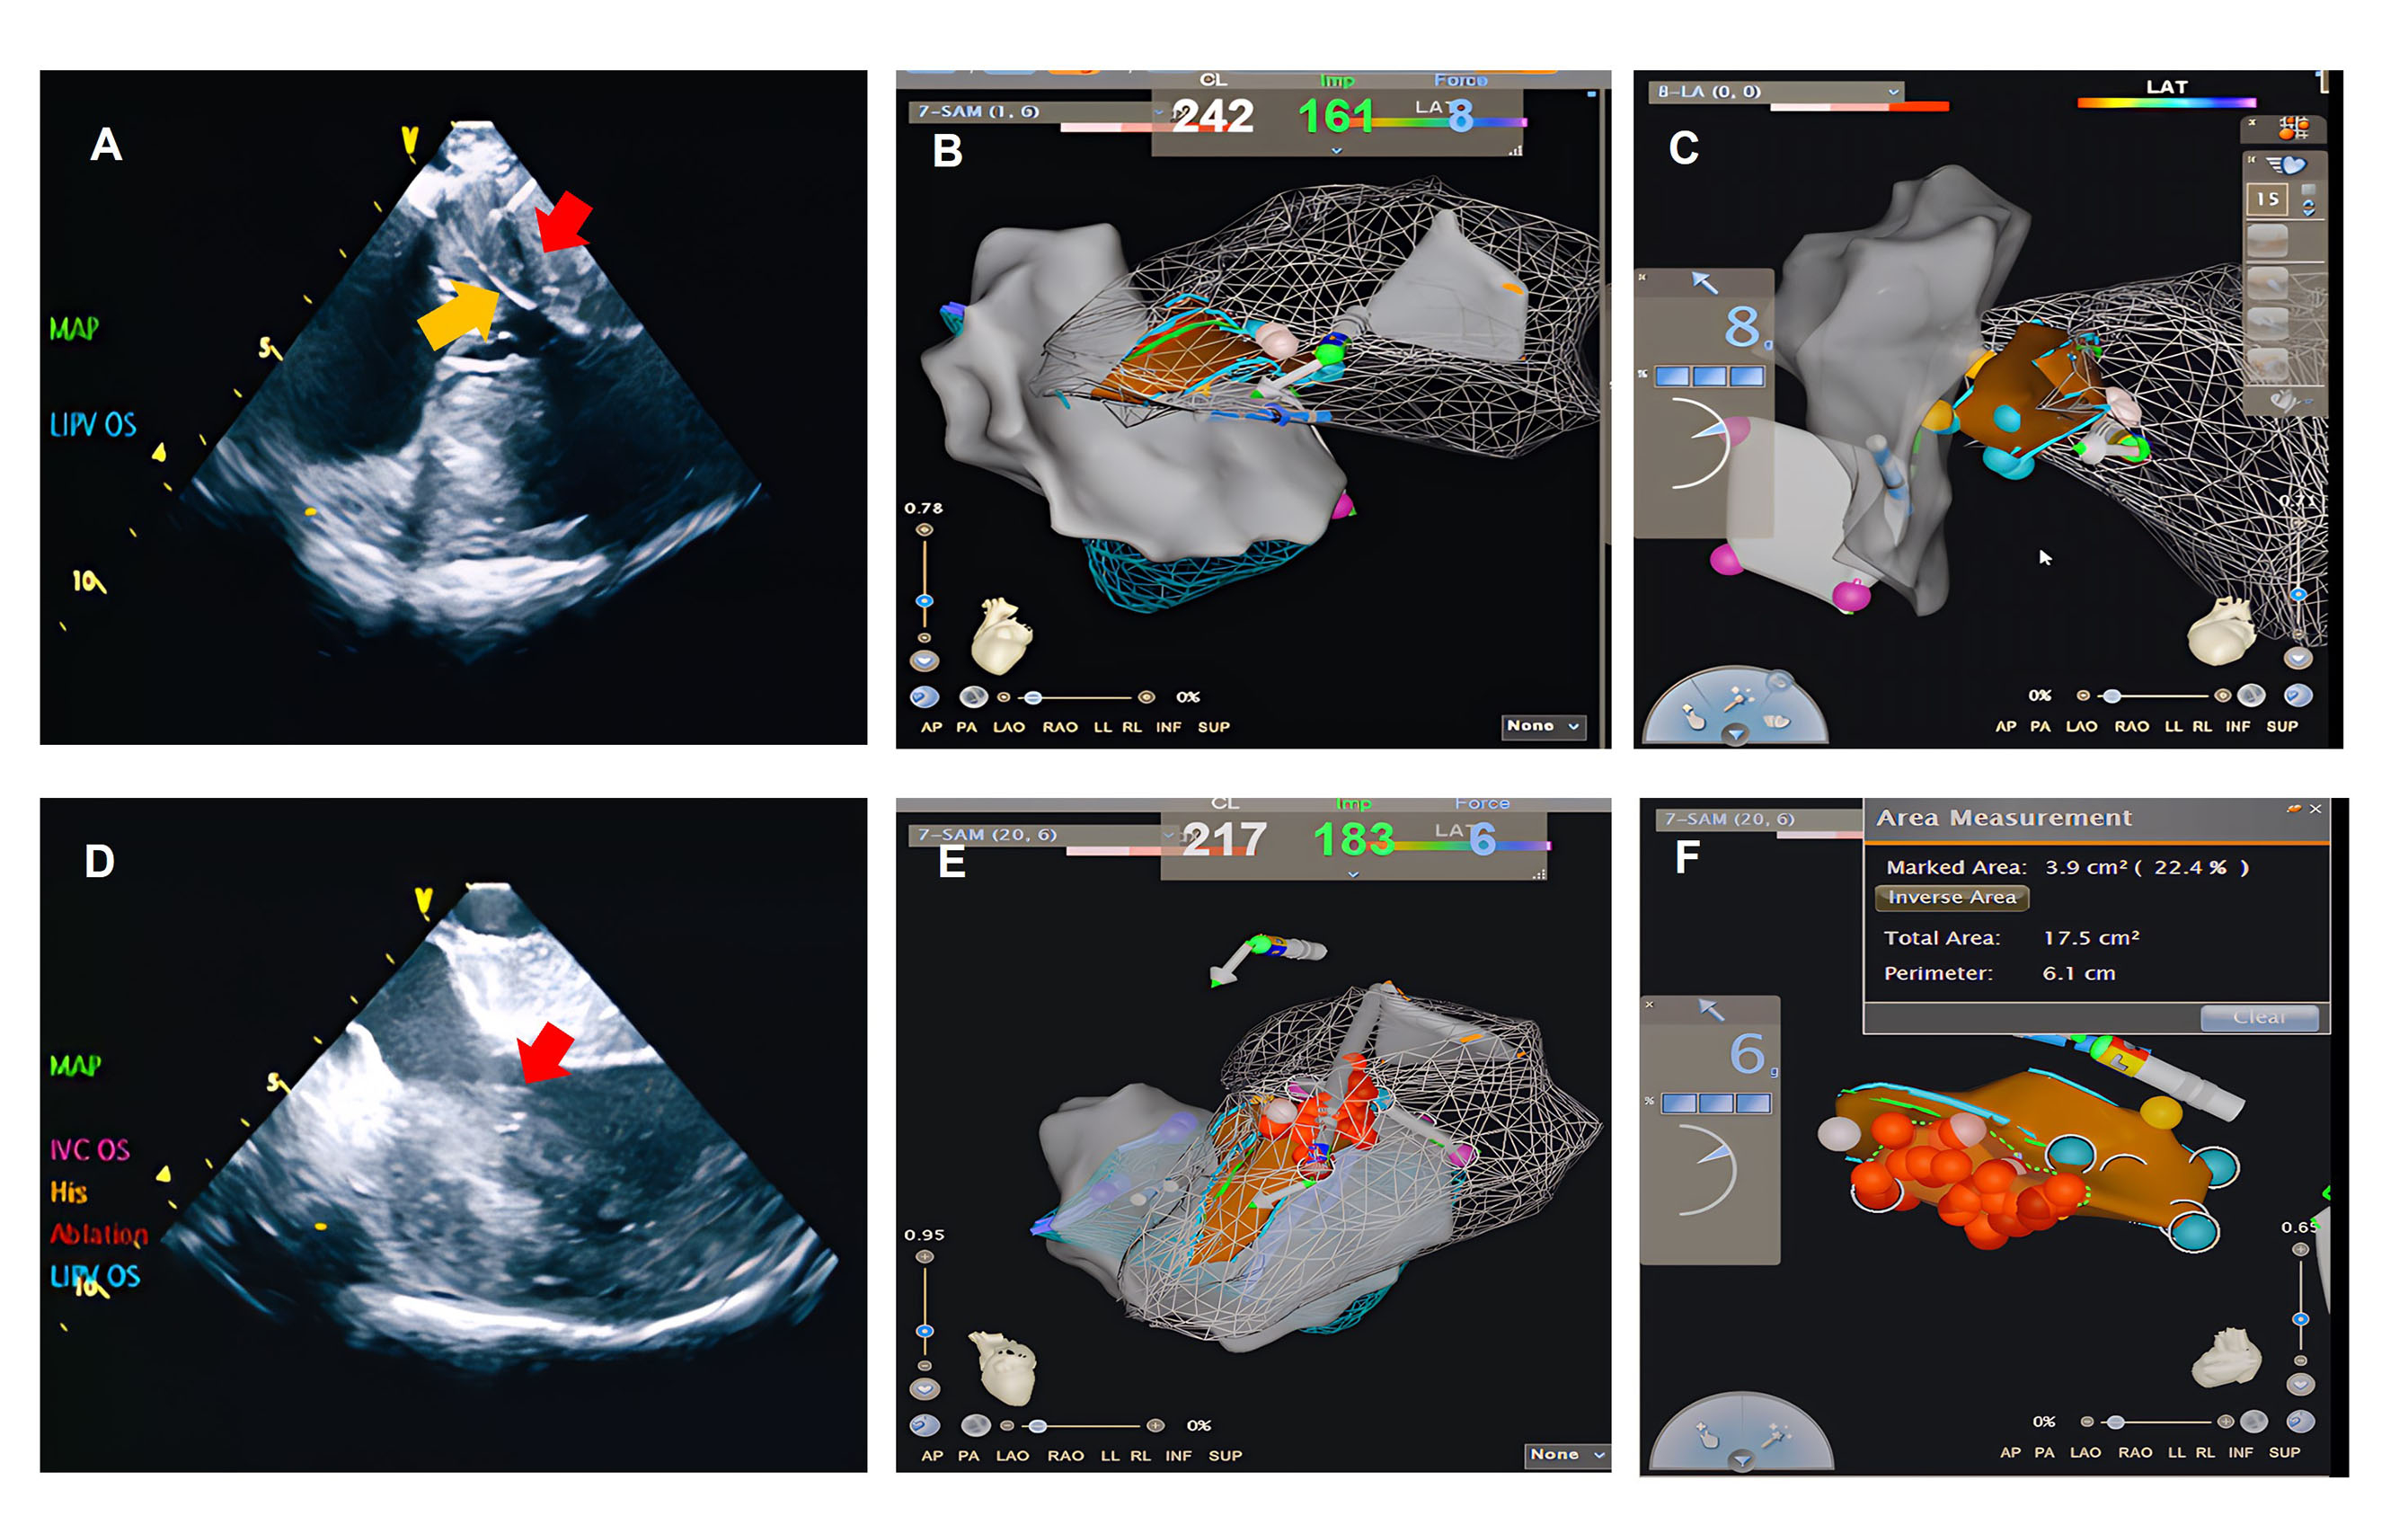

Methods: From March 2017 to November 2024, PESA was performed on 38 patients with hypertrophic obstructive cardiomyopathy at our center. The procedure was guided by a combination of a three-dimensional electrophysiological mapping system and intracardiac echocardiography (ICE). The primary outcome was the reduction in left ventricular outflow tract gradient (LVOTG) at 3 months or more post-PESA. Secondary outcomes included periprocedural major adverse clinical events and the need for surgical myectomy.